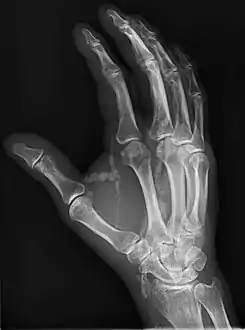

| Hand radiograph showing tumoral calcinosis, PA radiograph of the right hand showing tumoral calcinosis-like metastatic calcification in a patient on dialysis. Dialysis alters calcium phosphate product (>70). Idiopathic tumoral calcinosis is autosomal dominant and is not associated with dialysis. Note the premature arterial calcification which is a clue that this is a renal patient. Vascular calcification contributes to an increase in morbidity. | |